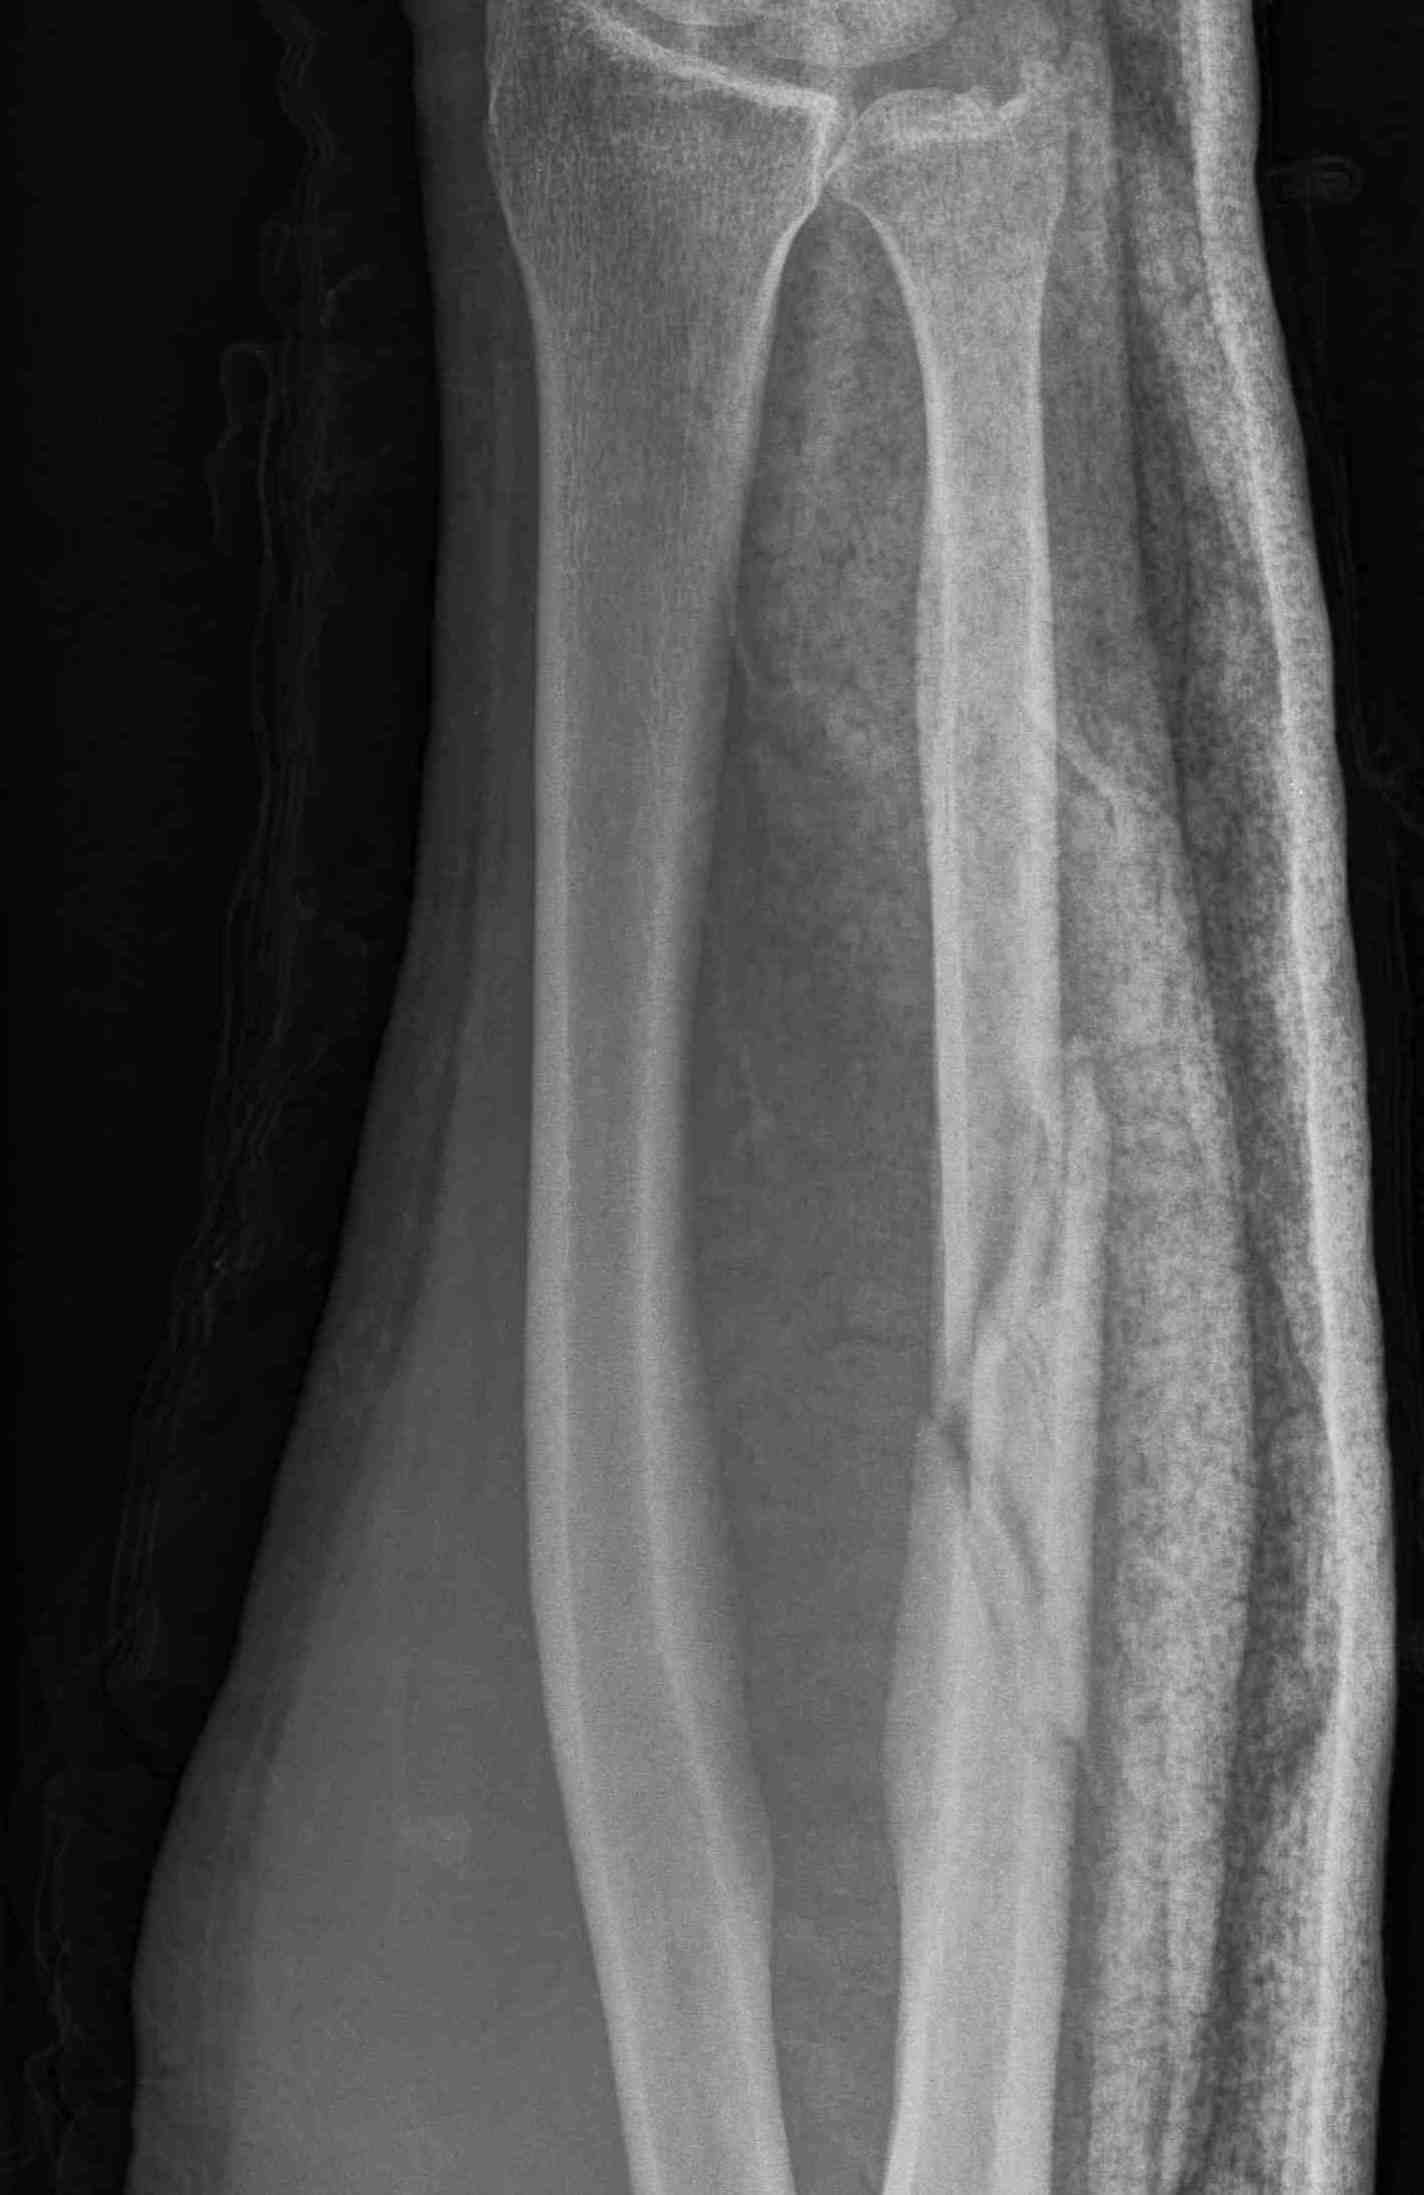

Acute fractures

- > 50% displacement

- > 10 degrees angulation

- midshaft ulna fractures - higher risk of nonunion